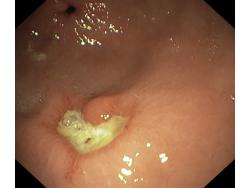

Wrzód trawienny